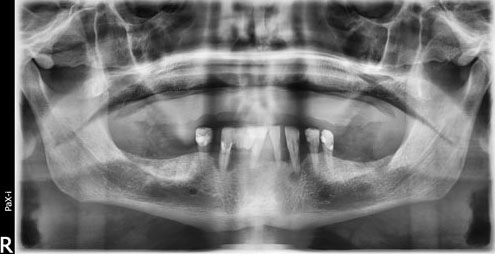

Case Report: The patient presented an increase in tissue volume in the papilla region between teeth 33 and 34, with no report of pain and with aesthetic impairment. Radiographically, no pathological changes were noted in bone and dental structures.